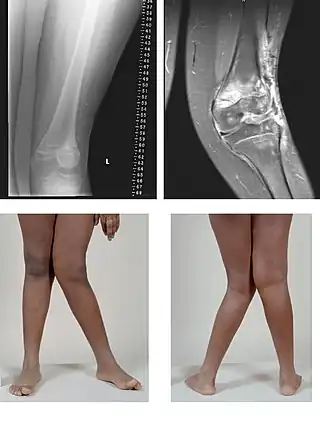

Genu valgum

El eje formado por el fémur y la pierna es más abierto de lo normal, adoptando el miembro inferior un aspecto en X con las rodillas muy juntas y los talones separados. Puede estar presente desde la infancia o aparecer en la vida adulta, muy frecuentemente causado por sobrepeso u obesidad.

Genu varum

En esta deformidad los miembros inferiores tienen una convexidad externa y los cóndilos femorales internos están separados por una distancia superior a los 6 cm. Es por lo tanto una desviación inversa a la que se produce en el genu valgum. Se describe a veces como miembros inferiores en paréntesis, pues los pies están muy próximos y las rodillas separadas en situación de bipedestación (de pie).